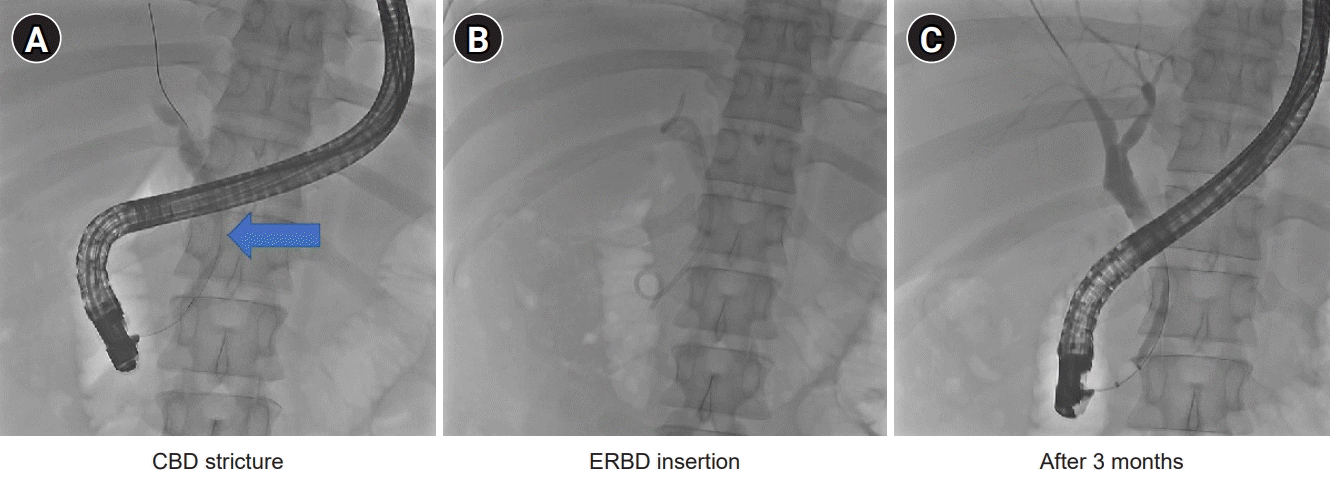

Chest radiography revealed the absence of active lesions. A chest CT revealed no active lesions. Abdominal CT revealed a large mass-like lesion in the pancreatic head and mild dilatation of the common bile duct (CBD). The distal CBD was encased in a mass-like lesion (Fig. 1). Magnetic resonance cholangiopancreatography showed a conglomerated mass with internal necrotic foci and infiltration of the caudate lobe of the liver. Moreover, it shows encasement of the CBD, portal vein, and celiac axis (Fig. 2). The endoscopic retrograde cholangiopancreatography (ERCP) showed a stricture in the mid-CBD. During ERCP, no significant resistance was observed after passing through strictures. Endoscopic ultrasound (EUS)-guided biopsy, brush cytology, and endoscopic retrograde biliary drainage (ERBD) were performed (Fig. 3). Before ERBD insertion, the peak total bilirubin was 6.79 mg/dL. AST and ALT levels were 466 and 801 U/L, respectively. After ERBD insertion, the total bilirubin level decreased to 1.00 mg/dL, and AST and ALT levels decreased to 27 and 65 U/L, respectively, on the 9th day after the procedure. An EUS-guided biopsy confirmed the superficially biopsied bile duct mucosa and benign-looking epithelial cell stripes. The cytological analysis revealed only a limited number of cells.

Due to the high possibility of lymphoma, an excision biopsy was performed on the neck LNs observed on PET-CT. After multidisciplinary care, excision biopsy was performed after discovering a hyperplastic mass located posterior to the internal jugular vein. AFB-positive bacilli were not identified. No fungi were identified using Periodic acid-Schiff or Grocott methenamine silver staining. However, nested-TB polymerase chain reaction (PCR) showed a positive reaction in the LNs. Therefore, the final pathological examination revealed granulomas in the LNs due to TB (Fig. 5). The patient was treated with anti-TB medications. Three months after ERBD insertion and anti-TB medication (isoniazid, rifampin, ethambutol, and pyrazinamide) administration, bilirubin levels and other liver function test results were normal. Strictures in the mid-CBD and lymphadenopathies improved.

Fig. 3.

Endoscopic retrograde cholangiopancreatography images. (A) A stricture in the mid-common bile duct (blue arrow). (B) Insertion of endoscopic retrograde biliary drainage. (C) After 3 months, the stricture was improved.